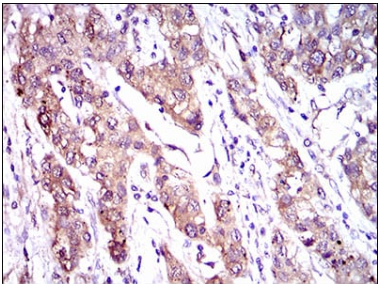

IHC    1/200 - 1/1000